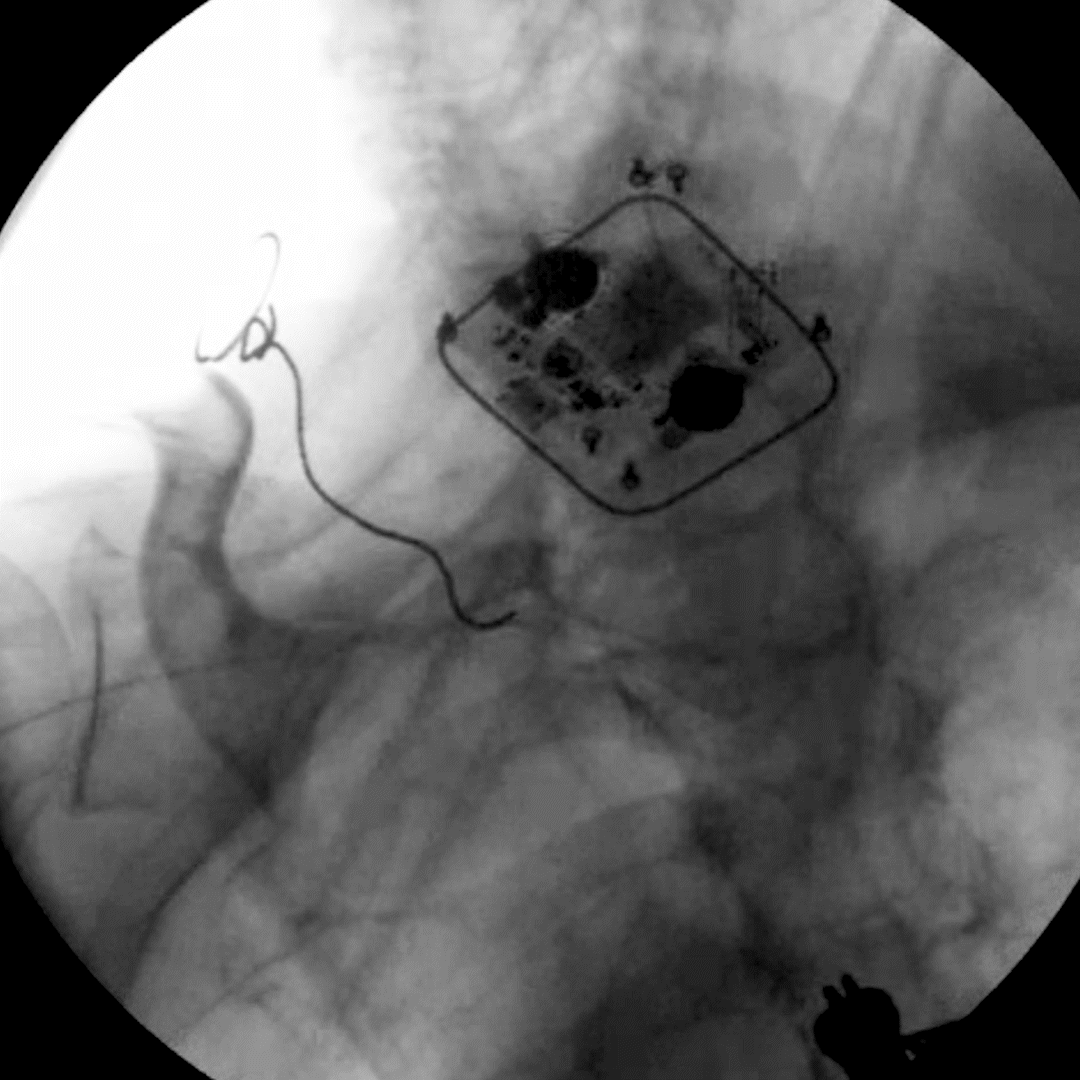

Neuromodulation devices targeting the dorsal root ganglion and nerves as well as nerve rootlets connecting into the DRG have technically challenging and time-consuming placement procedures. The Injectrode’s innovative placement procedure, with only 5 steps, has simplified how leads near the DRG can be placed. Relying on a transforaminal approach, similar to steroid injection pathways, present a development of a promising, minimally invasive alternative to the current standard of care.

The ‘scotty-dog’ landmark allows for repeatable injection of the device stimulator on the dorsal aspect of the roots as they exit the foramen. The delivery needle may be positioned between the likely location of the DRG and the pedicle at an oblique angle, then advanced off the bone to enter the dorsal aspect of the foramen. In this placement approach, the epidural space is not entered, and the Injectrode’s position relative to the ganglion enables stimulation.

Large animal and cadaver studies are underway to further characterize this placement approach.